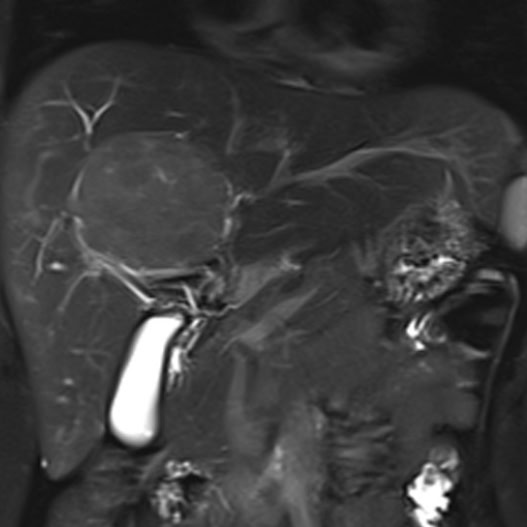

Conditions Detectable with Our Whole Body MRI

Whole Body Scan